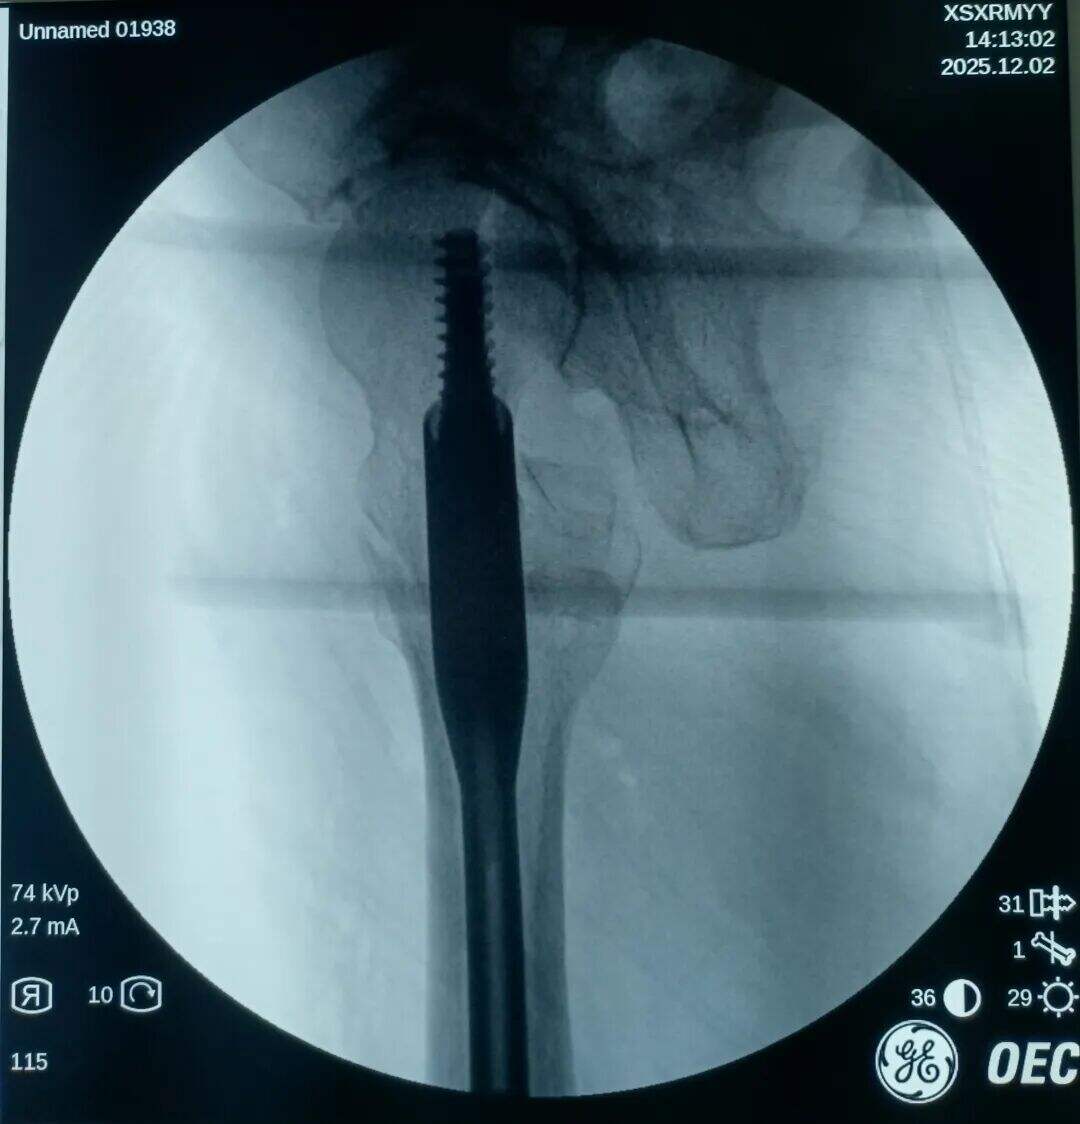

Narezen je bil 2 cm prednji mini-rez. Mesto zloma je bilo opazovano z prstom. Ugotovljeno je bilo, da je proksimalni fragment premaknjen navzgor, distalni fragment pa nazaj in zaklenjen. V mesto zloma je bil vstavljen klešča; pod vodstvom prsta v kombinaciji s kleščo so bili zaklenjeni fragmenti odklenjeni. Nato je bila klešča uporabljena za ohranitev kakovosti redukcije z medialno in lateralno kompresijo. Izvedena je bila običajna lokalizacija, vstavitev vodilne žice ter standardni kirurški postopek.

Medularni kanal je bil ozek. Nobenega razširjanja ni bilo izvedeno. Intramedularni klin s premerom 9 mm je bil vstavljen v tesen fit. Prilagoditev anteversije cefalomedularnega vijaka se je izkazala za težko.